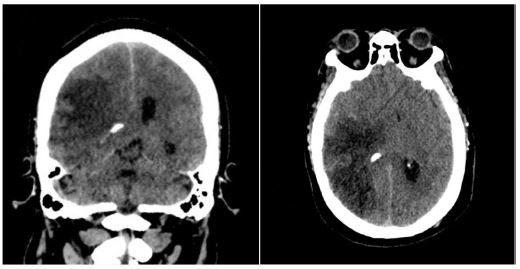

Twenty-four hours post-admission, his neurological status worsened (GCS decreased by 4 points), and a CT scan showed a significant midline shift. A right-sided frontotemporoparietal decompressive craniectomy was performed. Postoperatively, his GCS improved to 14 and motor strength improved to 3/5 on the Lovett scale (Figure 2). A Computed Tomography Angiography (CTA) performed 48 hours after surgery showed restored flow in the M1 and distal branches of the right MCA (Figure 3). A confirmatory cerebral angiogram at two weeks demonstrated patent flow throughout the MCA distribution (Figure 4).

Upon discharge, the patient had an ECG score of 15, a Karnofsky Performance Score of 70, and residual hemiparesis of 3/5. At a three-month follow-up, he had improved to a Karnofsky score of 90 and 4/5 strength in the left upper limb, with persistent left facial nerve palsy (Figure 5).

Figure 4: Cerebral angiography 2 weeks later, showing recanalization of the right MCA.